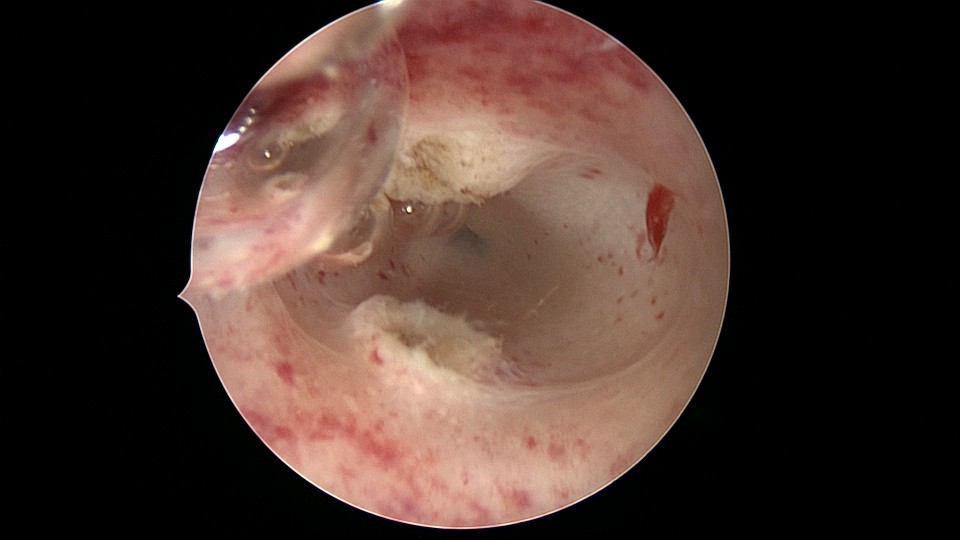

患者21岁,G2P0,两次胎停清宫,月经量减少,眉山某医院B超示宫腔容积小,2021年7月宫腔镜探查,见宫腔两侧、宫底部及左侧宫角粘连,单极电针分粘,恢复宫腔形态,显露双侧输卵管开口。2021年9月宫腔镜二探取球囊,宫腔形态正常,双侧输卵管开口可见。2022年9月自然妊娠12+周,我院建卡,2023年5月孕38+周剖宫产分娩。2025年3月宫腔镜取胚1次,现25岁,G4P1,剖宫产1次。